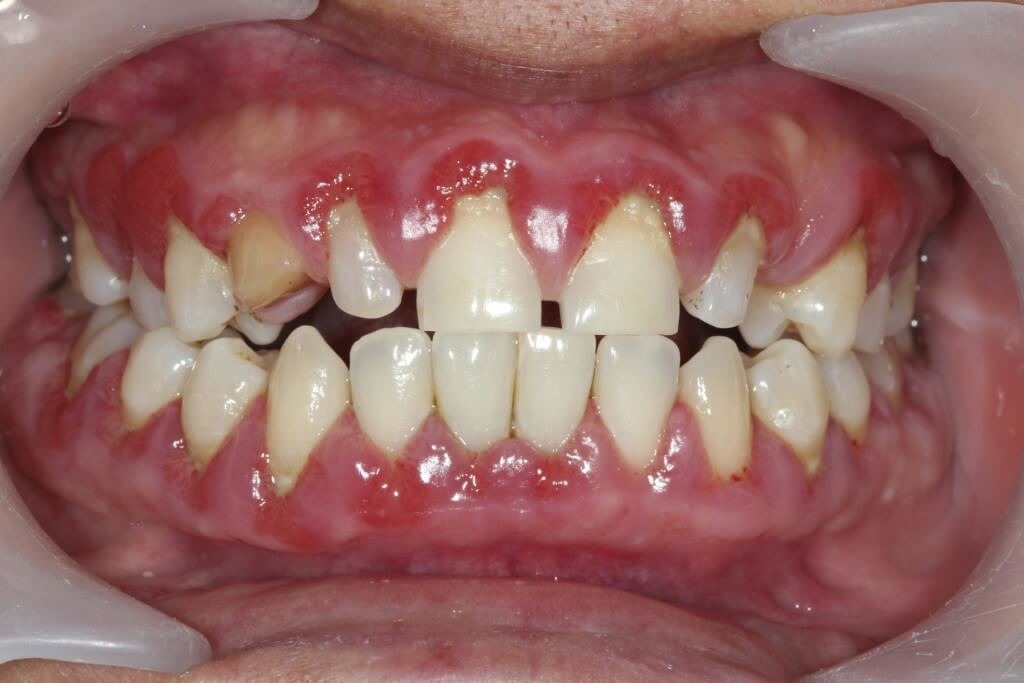

La gingivite, une inflammation des gencives, peut avoir des conséquences significatives sur la santé bucco-dentaire.

La principale cause de la gingivite est l’accumulation de plaque dentaire. Cette fine couche composée de bactéries et de débris alimentaires se forme constamment sur les dents. Si elle n’est pas éliminée efficacement par un brossage régulier, elle peut irriter les gencives, déclenchant ainsi une réaction inflammatoire.